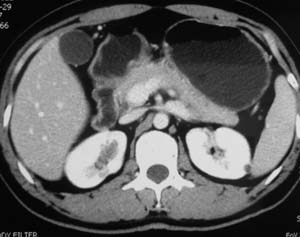

以下是引用子期在2010-3-19 20:47:00的发言:[br]血管畸形的ct增强应该有明显强化,本例并不相符合。本例双肾局部的略低密度影,累及肾盂,局部皮质明显变薄、内陷,增强扫描有轻度的强化,应考虑为炎性病变,患者为年轻男性,累及双肾的感染以结核较常见,可以没有明显的临床症状,尿中有时候也并不能查出什么;肾脓肿常有明显感染中毒症状,本例不符,另外一般的肾盂肾炎或肾小球肾炎通过小便就可确诊,其它还不能排除的是黄色肉芽肿性肾盂肾炎,然而单凭ct一般也很难鉴别。